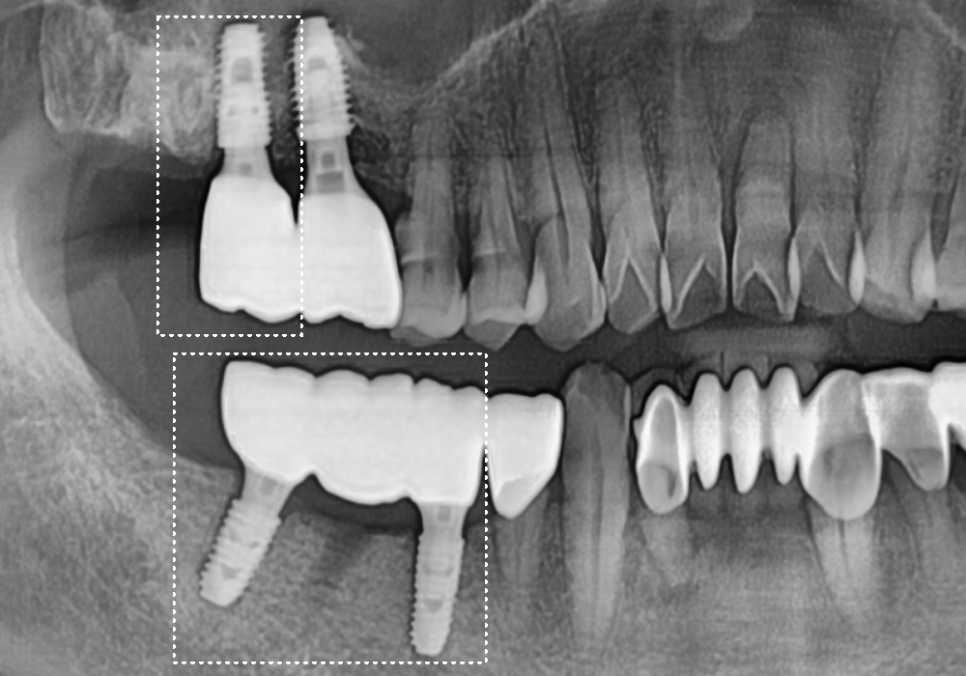

우선 오래된 브릿지를 조심스럽게 제거한 뒤

이미 제 기능을 잃고 뿌리만 남은

#46번 치아는

발치를 진행하기로 결정했습니다.

그 대신 오래전부터 치아가 상실되어

공간이 비어있던 #45번과 #47번 자리에는

튼튼한 임플란트를 심어

새로운 뿌리를 만들어드렸죠.

아래쪽 임플란트(#45~47)는 다행히 뼈가

아주 튼튼한 상태라

별도의 뼈이식 없이 진행했습니다.

한 달 뒤, 지르코니아 보철물까지

완벽하게 완성해 드렸죠.

상악동 거상술을 함께 했던 위쪽 치아는

조금 더 여유를 두었습니다.

4개월 뒤에 튼튼하게 자리 잡은 것을 확인하고

보철물을 올려 마무리해 드렸습니다.